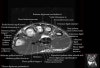

- Axial section

Axial T1 evaluates the tendons of the wrist and carpal tunnel, including the flexor retinaculum.

Axial PD fat suppressed evaluates the tendons of the wrist and carpal tunnel, including the median nerve.